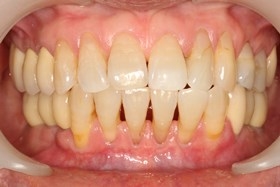

因植牙恢復正常咬合